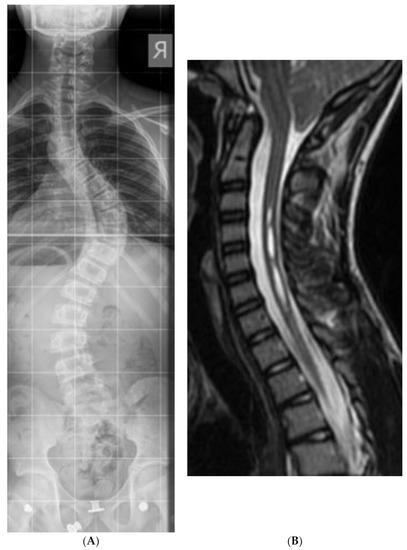

From November 2011 to December 2018, we identified 15 patients with Chiari malformation type 1 and scoliosis; the average age was 12.7 years (5–19). Scoliosis cases included eleven AIS, two congenital/EOS, and two syndromic (Figure 1A,B). Eleven CM-1 patients were symptomatic; nine of the eleven suffered from headaches, two of the eleven had extremity motor weakness, and four of the eleven suffered headaches and vomiting. The cohort did not suffer from visual disturbances. The symptoms described were considered an indication of posterior fossa decompression. Four were asymptomatic and were followed up. Eleven of the fifteen CM-1 patients had syringomyelia; the other four patients consisted of three with AIS and one with congenital scoliosis. The three AIS patients required scoliosis correction following PFUCD, while the congenital scoliosis was treated conservatively. The average post-operative follow-up was 26.2 months (with a range of 6–59 months). Post-operatively, all patients improved significantly, with two patients reporting a complete resolution of their symptoms. One patient suffered a superficial surgical-site infection that was treated successfully with oral antibiotics. Seven patients underwent scoliosis surgery, and in six of them, PFUCD was performed prior to the scoliosis correction (all were AIS cases). Only one case of scoliosis was operated on in the presence of a mild CM-1 who was treated conservatively (Table 1).

Figure 1. (A) Thirteen years old AIS patient with CM-1—AP Spine. (B) Thirteen years old AIS patient with CM-1—Cspine MRI.